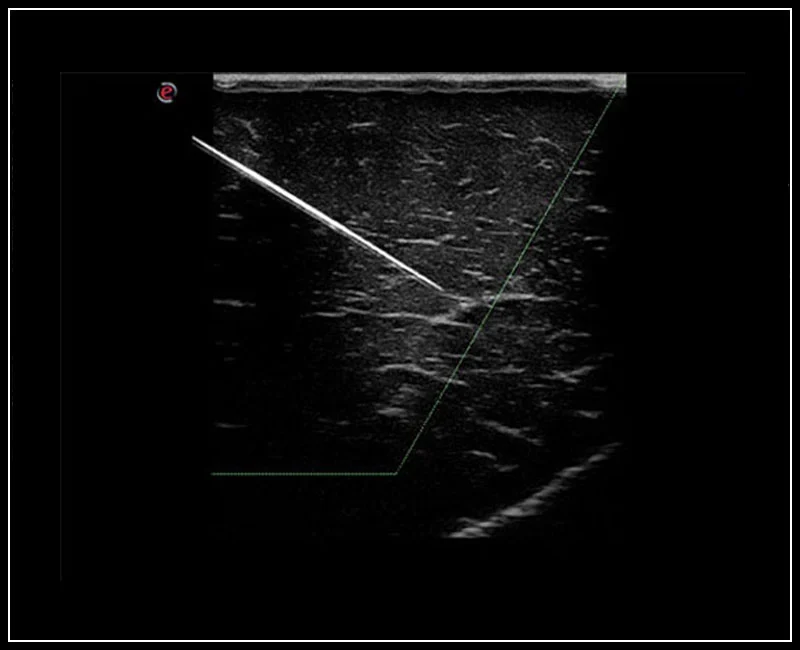

MyLab™Sigma Elite - Needle Enhancement for precise interventional procedures

MyLab™Sigma Elite - Needle Enhancement for precise interventional procedures